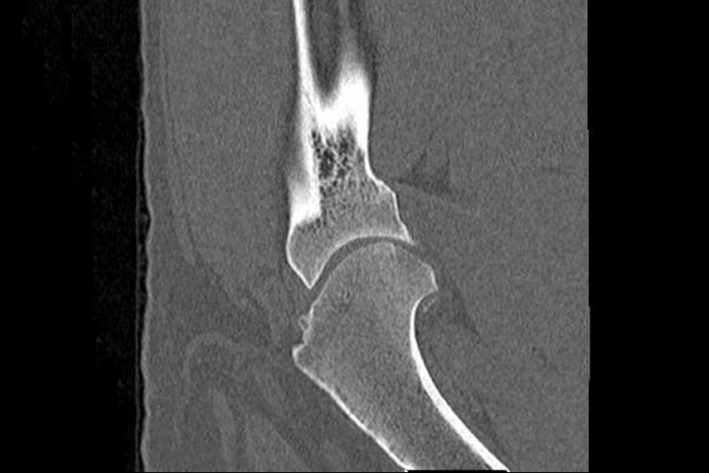

Die Diagnosestellung erfolgt in der Regel während einer orthopädischen Untersuchung durch Ihren Tierarzt in Kombination mit Röntgenbildern und/oder CT.

Die wichtigste Differentialdiagnose stellt eine Coronoiderkrankung oder OCD im Ellbogengelenk dar. Nicht selten gibt es auch Hunde, die an beiden Erkrankungen parallel leiden, wobei die Ellbogenerkrankung meist die schlimmere ist. In vielen Fällen wird daher zum Ausschluss auch ein CT der Ellbogengelenke angefertigt werden.

CT OCD